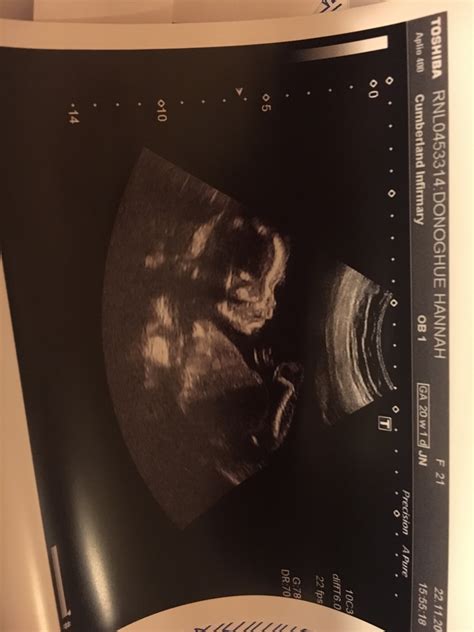

Navigating the world of pregnancy can feel like traversing a minefield of anxieties, especially when it comes to those crucial ultrasound scans. One such scan, the 20-week anatomy scan, is a significant milestone. It’s a detailed check-up, where sonographers meticulously examine your baby’s development. But what happens when this scan brings unexpected news? Discussions around terms like OSCIPSEC and experiences shared on platforms like Reddit can add layers of complexity and, let’s be honest, a fair bit of stress. Let’s dive into what OSCIPSEC might mean in the context of a 20-week scan and how to make sense of information found on Reddit, while keeping a level head.

Understanding OSCIPSEC in the 20-Week Scan Context

Okay, guys, let’s break down this term “OSCIPSEC.” In the world of medical jargon, abbreviations and acronyms are super common, but they’re not always super clear to those of us outside the medical field. Without specific context, OSCIPSEC isn’t a widely recognized medical term. It might be a typo, a local abbreviation used within a specific hospital or clinic, or even a term specific to a research study. The important thing is not to panic! If you’ve encountered this term in your own scan report or during a consultation, the best course of action is always to ask your healthcare provider directly. They can provide clarity on what it means in your specific case. Remember, self-diagnosing or relying solely on internet searches can lead to unnecessary worry. Your doctor or sonographer is the most reliable source of information about your baby’s health and development. They can explain the findings of your scan in detail and address any concerns you may have. Think of them as your personal pregnancy gurus, there to guide you through this journey!